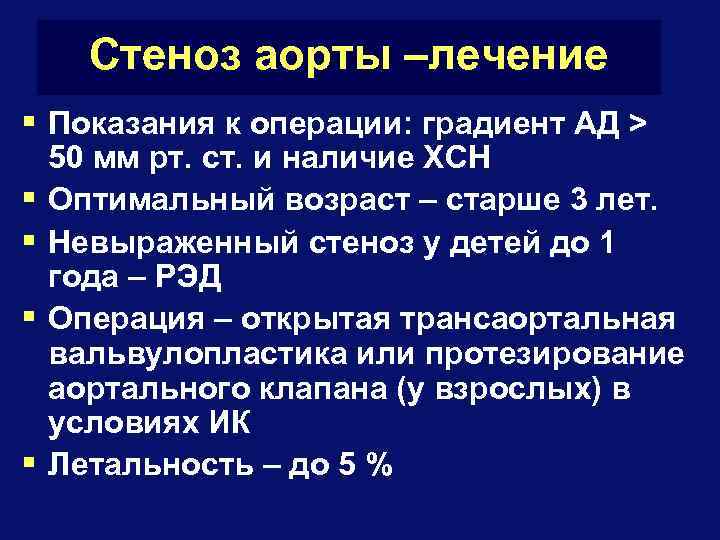

Стеноз аорты –лечение § Показания к операции: градиент АД > § § 50 мм рт. ст. и наличие ХСН Оптимальный возраст – старше 3 лет. Невыраженный стеноз у детей до 1 года – РЭД Операция – открытая трансаортальная вальвулопластика или протезирование аортального клапана (у взрослых) в условиях ИК Летальность – до 5 %